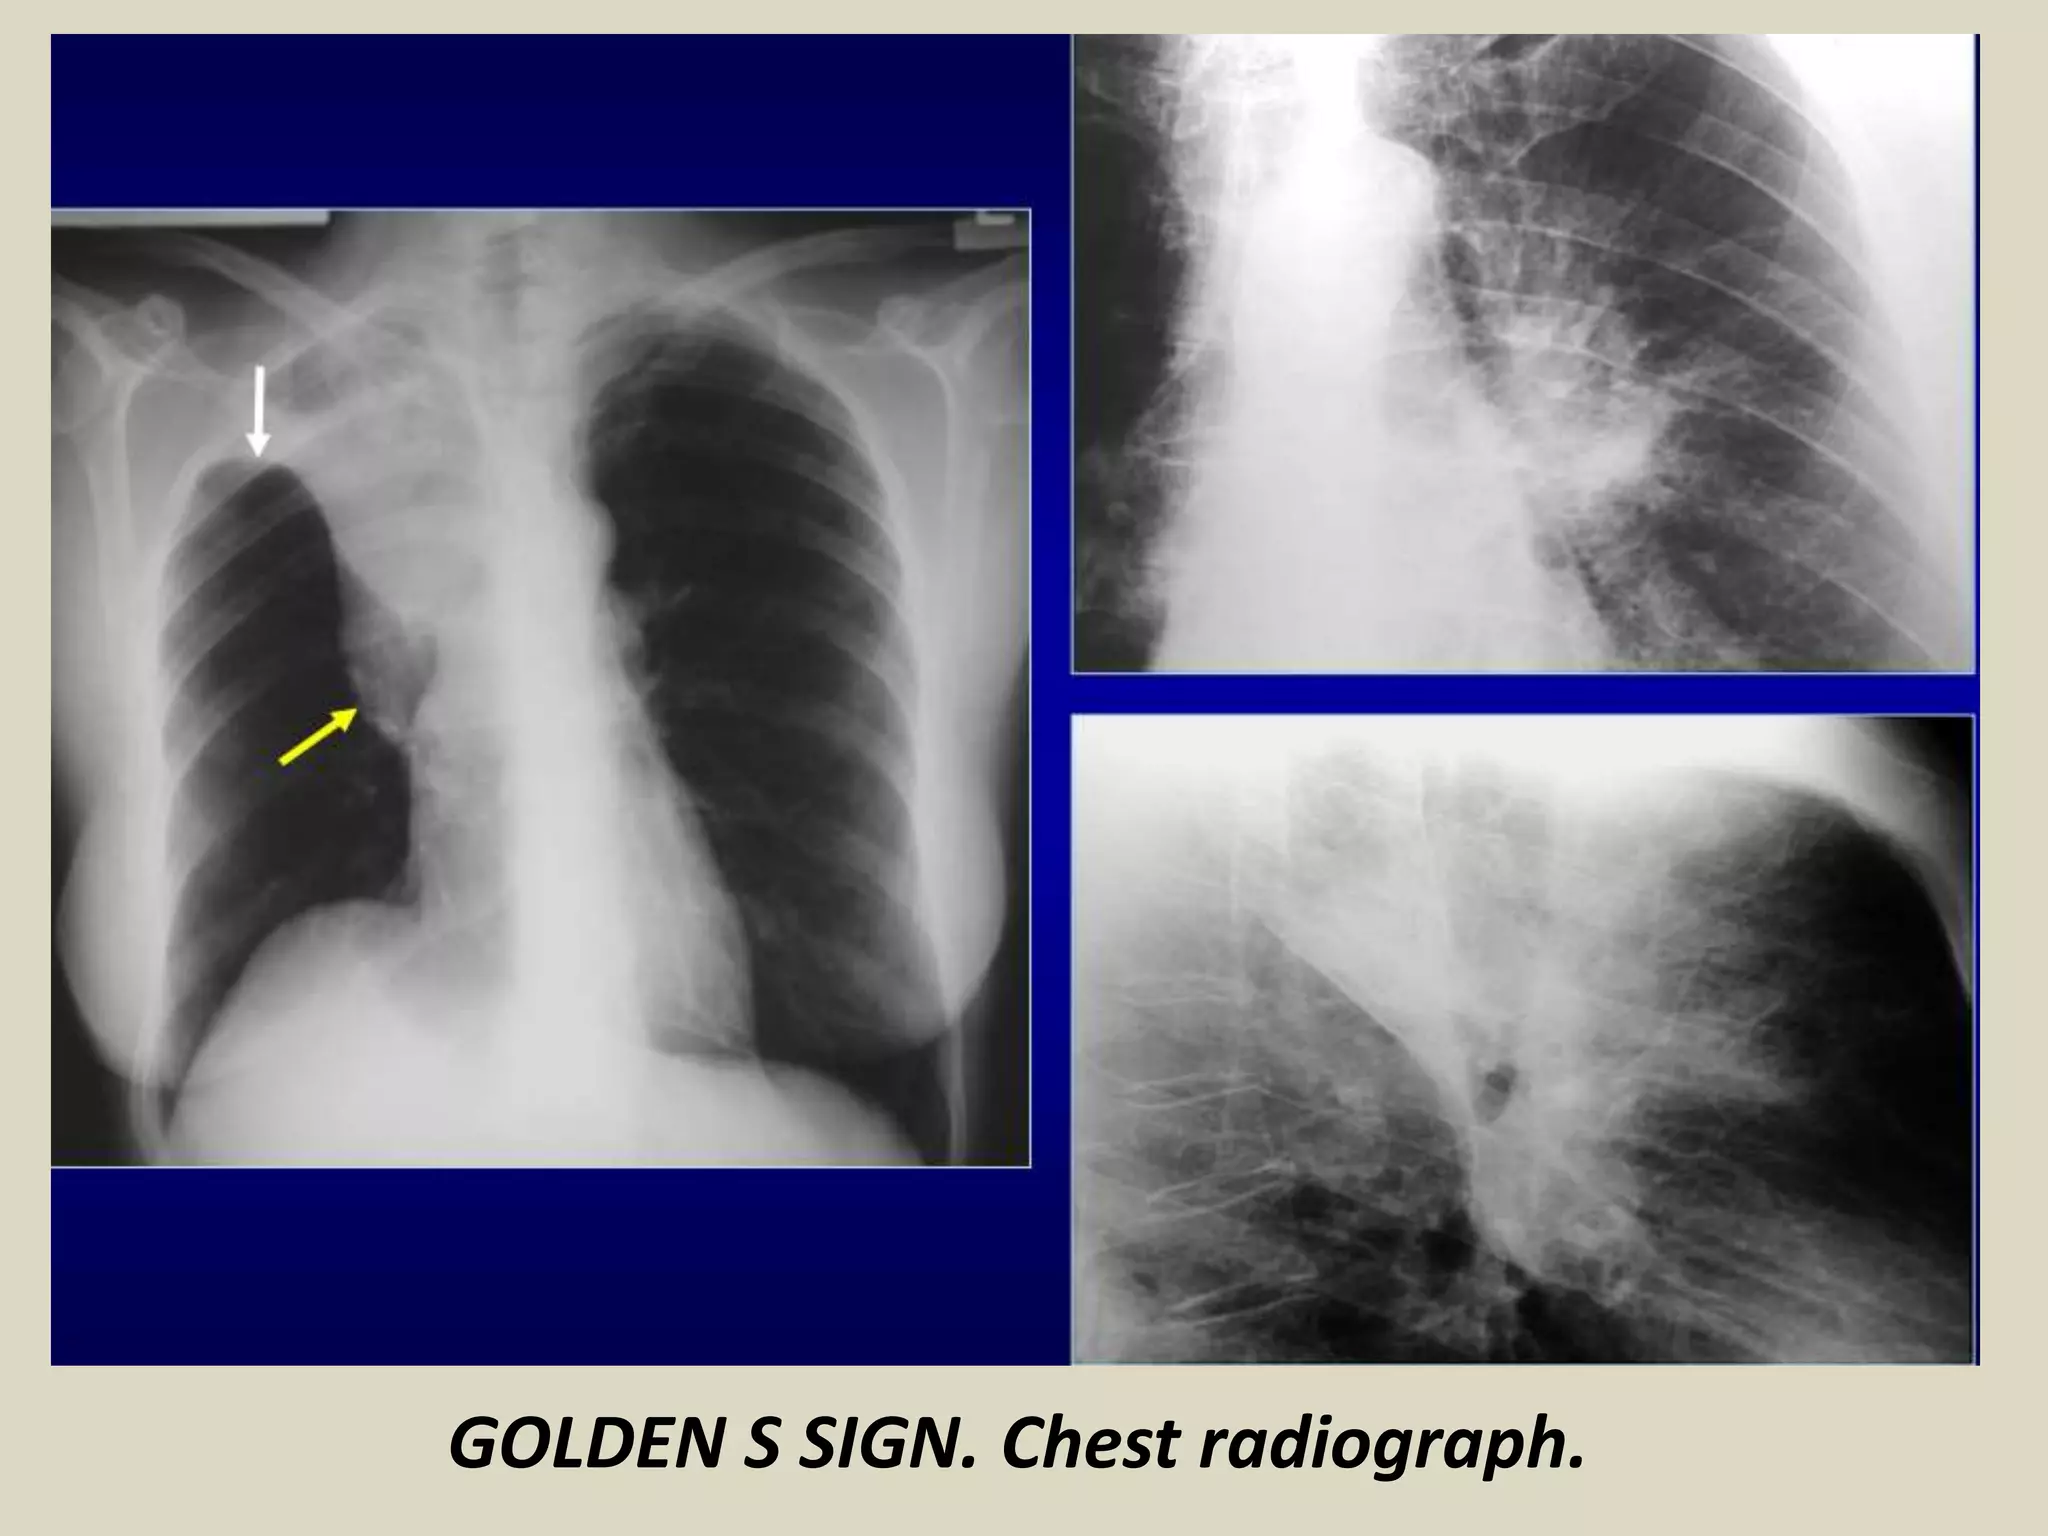

GOLDEN S SIGN

Described by Ross Golden in 1925

Resembles a reverse S shape

It can be seen on PA/lateral views and CT

This sign is typically seen with right upper

lobe collapse

The medial portion of minor fissure is convex

inferiorly due to a central mass and the lateral

portion of the fissure is concave inferiorly

It can be observed in cases of bronchial

carcinoma, primary mediastinal tumor,

metastasis and enlarged lymph nodes

GOLDEN S SIGN. Chest radiograph and CT images

demonstrate this sign. Bronchial carcinoma.

GOLDEN S SIGN. Chest radiograph.